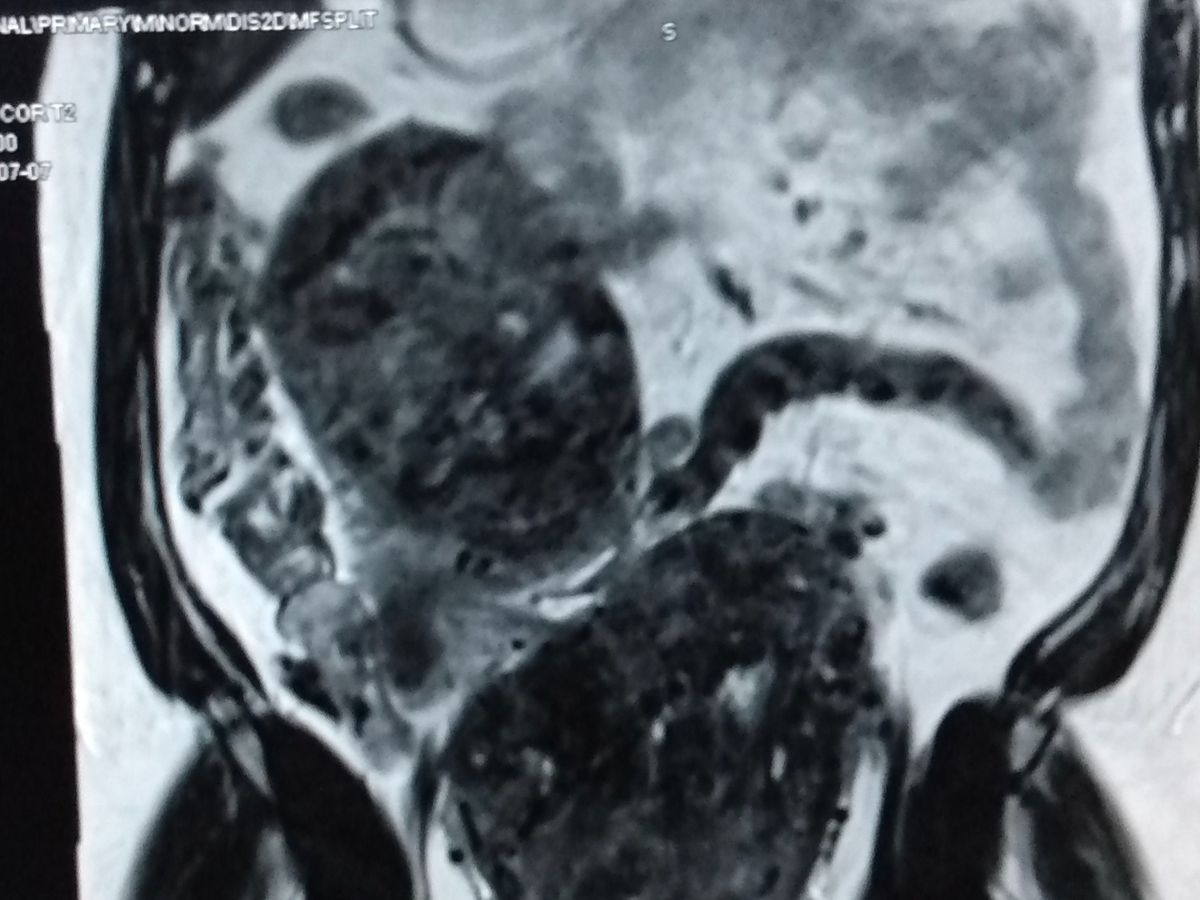

Hi, My name is Charlet Dupar, and I am fundraising for emergency surgery to remove two life-threatening fibroids. One is pushing up my liver out of place and suffocating my right kidney. According to my doctor, it will lead to kidney failure. The other is sitting on my colon and bladder. They are 15cm, about 15lbs each. They've made my 4ft 9 frame look like I'm 28 weeks pregnant.